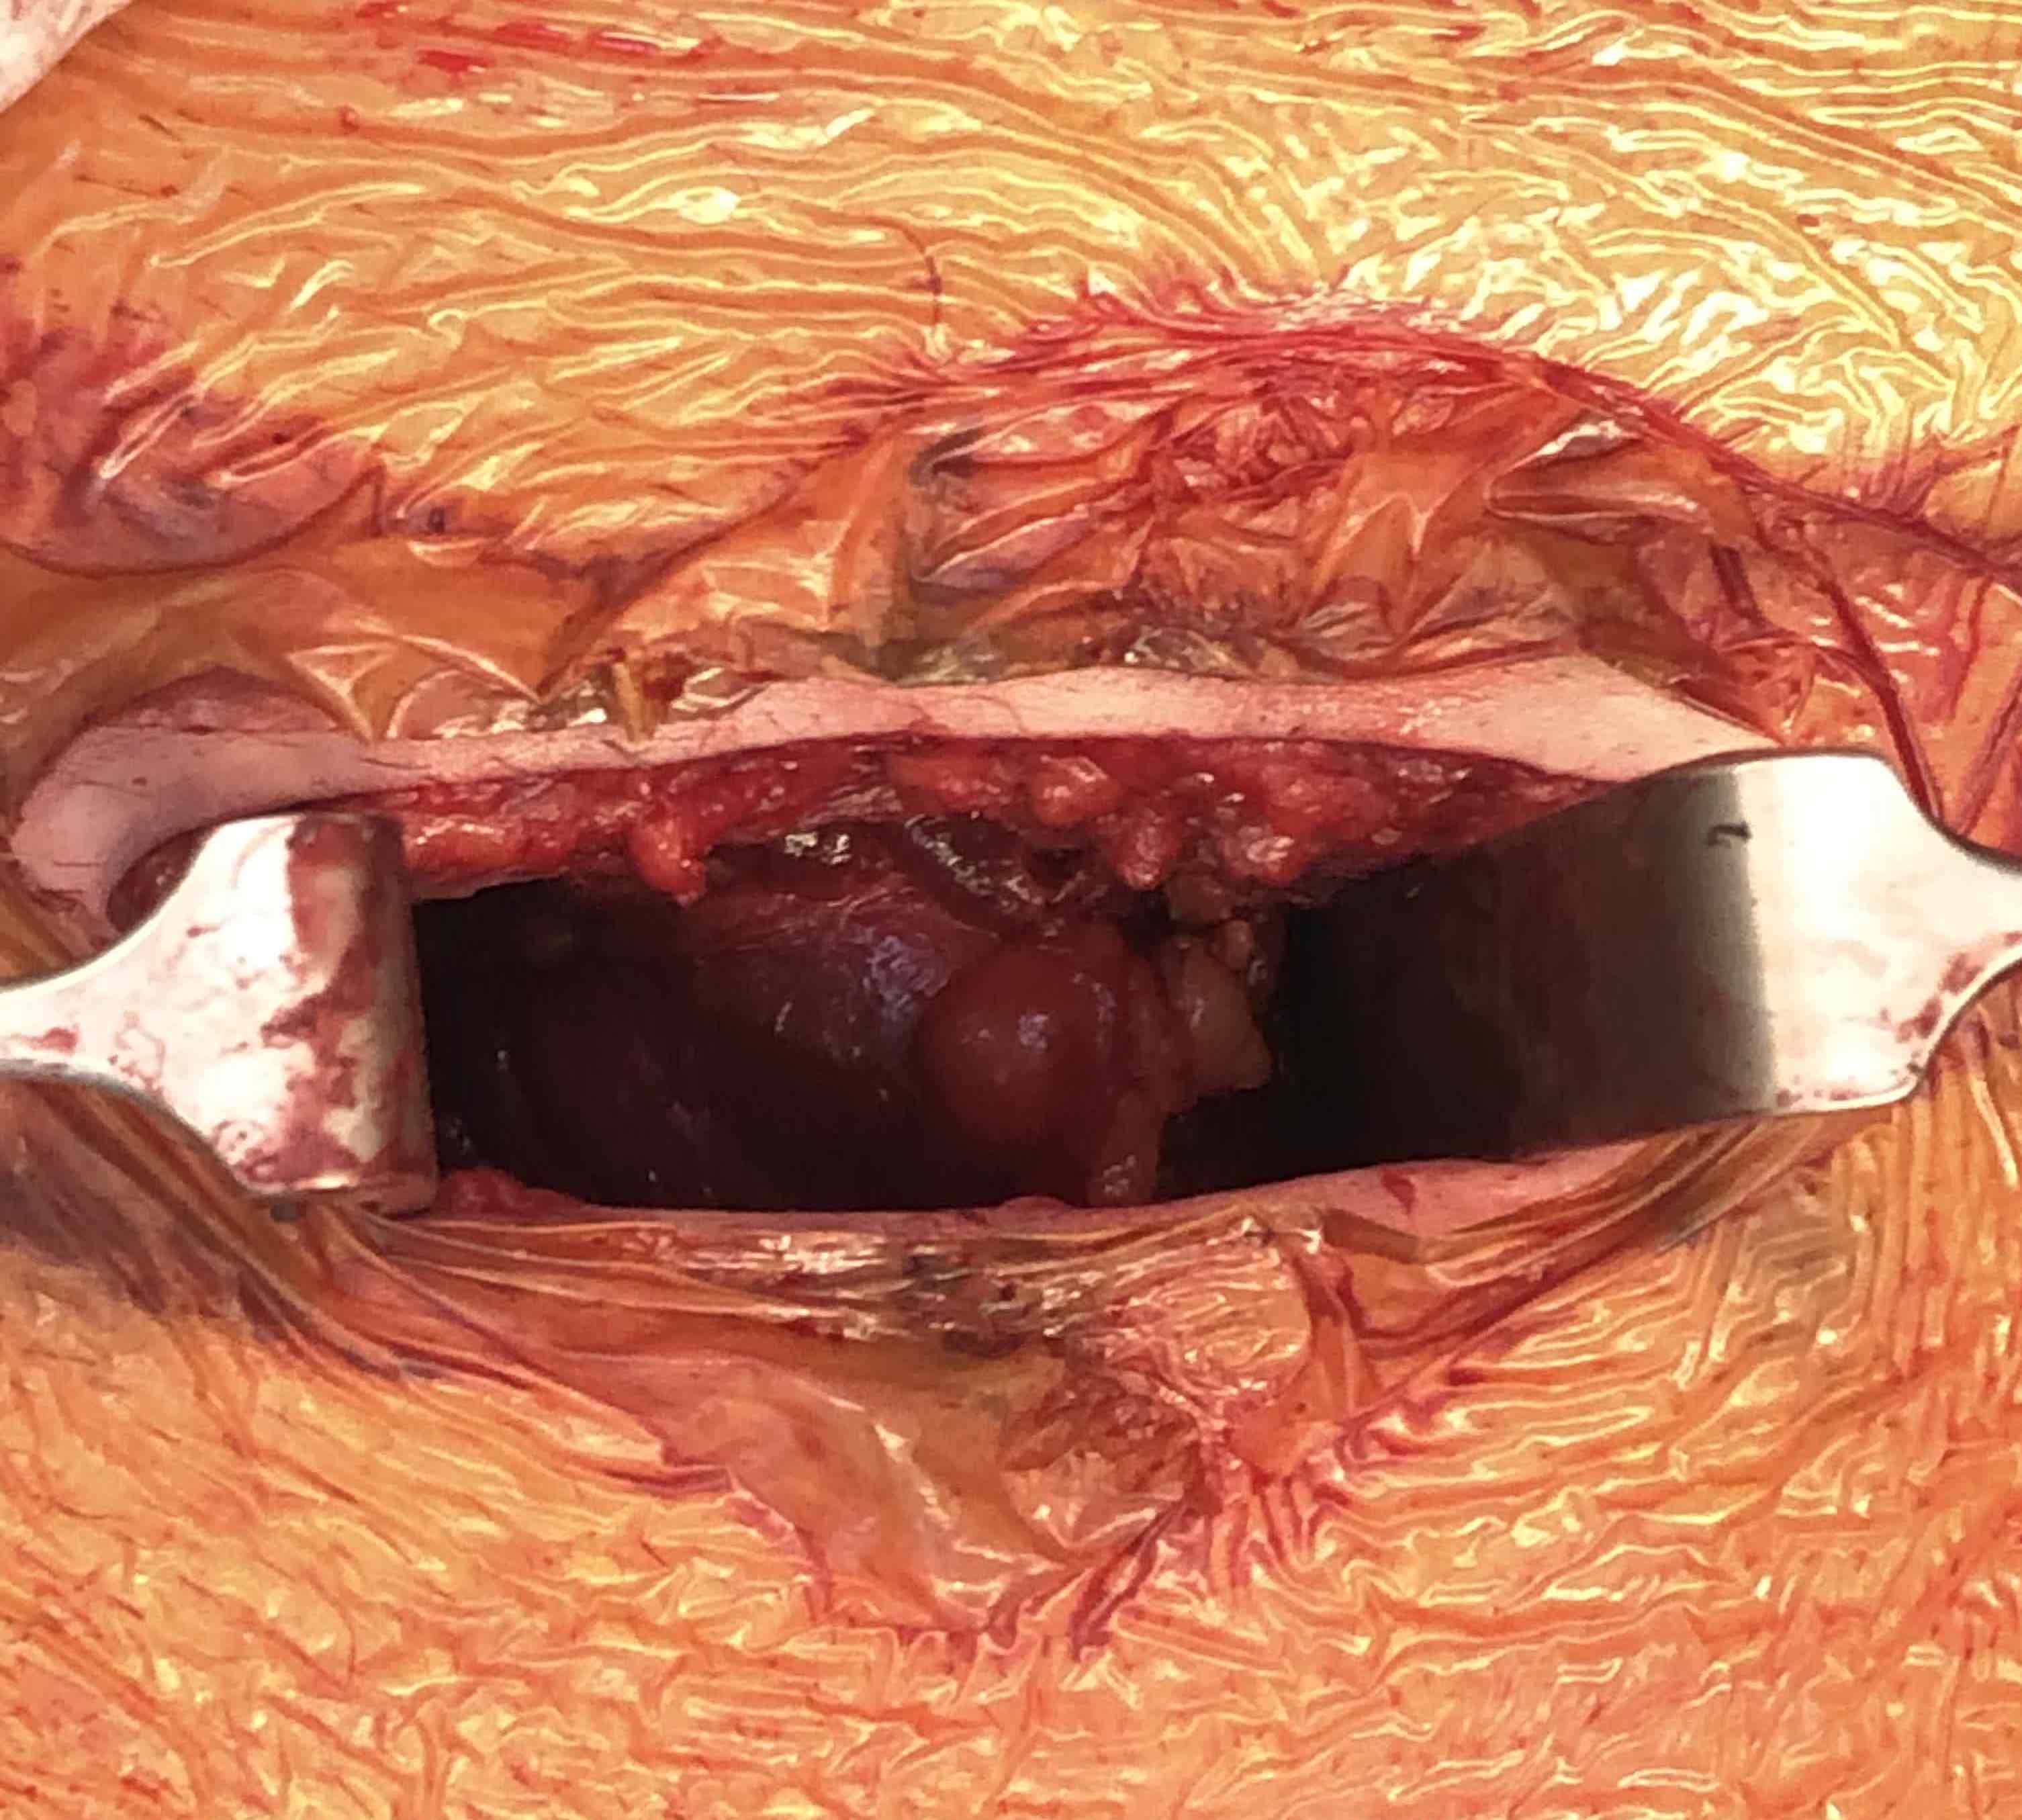

Pfannenstiel approach / Plating Pubic Symphysis

Incision 2 cm above pubis

- through fat and fascia

- split linea alba between rectus

- identify and protect bladder

Incision 2 cm above pubis Identify linea alba and develop plane between rectus

Identify and protect bladder posteriorly